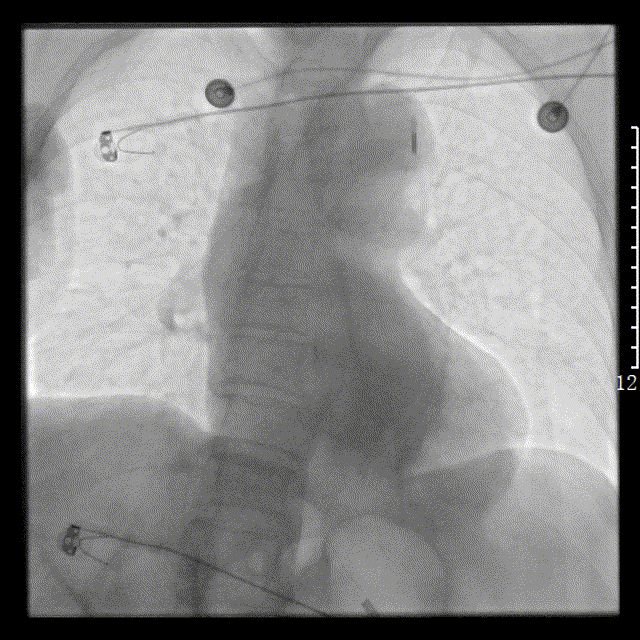

左图:选择6F SAL1.0指引导管,放至右冠状动脉开口,将Runthrough钢丝放至右冠状动脉远段。

右图:以博迈Artimes 2.0×20mm球囊对右冠状动脉中段病变进行扩张,造影见右冠状动脉血流恢复,血流缓慢,可见血栓影。

左图:以泰尔茂EXTRACTOR抽吸导管反复进行血栓抽吸。造影见右冠状动脉远段不显影。

右图:将北芯True Reach双腔微导管送至右冠状动脉远段,通过微导管注射替罗非班注射液500ug及硝酸甘油50ug。

右冠远段血流恢复,PDA近段90%局限狭窄,先后以 2.0×20mm球囊及2.5×10mm棘突球囊对后降支近段病变处进行扩张。右冠状动脉血流恢复,血流TIMI3级。术中患者心率慢、血压低,予阿托品注射液0.5mg静脉注射,予去甲肾上腺素持续静脉泵入并间断予间羟胺注射液静脉注射。术后经左侧股动脉行主动脉内球囊反搏。术中共用碘克沙醇90ml。术毕安全送至ICU病房。